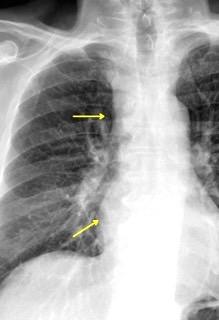

Síntomas y signos que se producen con la obstrucción total o parcial de la vena cava superior

Causas Malignas +/- 90-95%

Ca. Broncogénico (80-85%)

Linfoma No Hodgkin (15%)

Catéteres, shunts y marcapasos…23%

T. Mediastínico. Bocio

Fibrosis Idiopática

Tb, Histoplasmosis, Actinomicosis, Sarcoidosis

Carcinoma microcítico con síndrome de VCS

Grupos:

1. Obstrucción por encima de la V Ácigos. (La sangre llega al corazón a través de ella)

2. Obstrucción con participación de la V. Ácigos. (La sangre utiliza otras alternativas para llegar al corazón vía VCI).

Participación de la V. Ácigos como vía principal para llegar a la VCI.

Visible: 88%